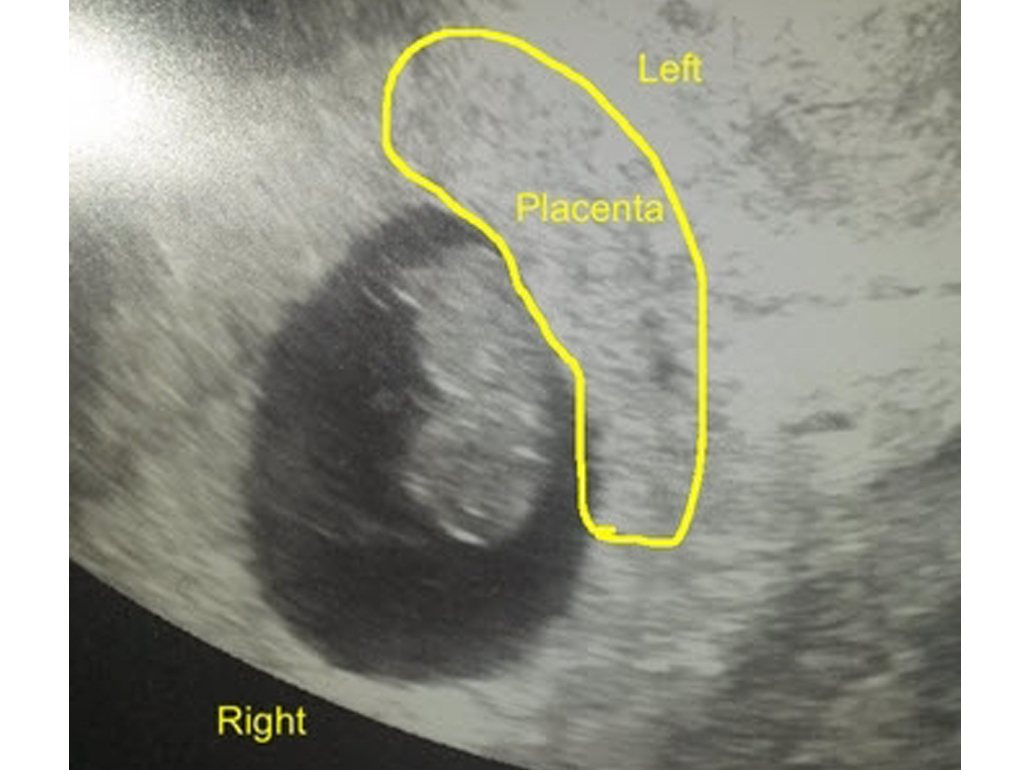

Ramzi teorisi cinsiyet belirleme konusunda ilerleyen zamanlarda plasentaya dönüşecek olan koryonik villusun konumunu baz alıyor. Ancak koryonik villus, 8. haftadan sonra biçim değiştireceği için bu tahminin 6-8 haftalar arasında yapılması gerekiyor.

- Ramzi teorisine göre cinsiyet tahmini, 2 boyutlu ultrason görüntüsü incelenerek yapılıyor.

- Bu teoriye göre koryon villusun konumu kromozomlarla alakalı.

- Buna göre ultrasonda minik, parlak bir nokta olarak görünen koryon villus, rahmin sağ tarafında ise XY yani erkek, rahmin sol tarafında ise XX yani kız kromozomları taşıyor şeklinde yorumlanır.

Ultrasonda bu durum, yalnızca bir uzman tarafından yorumlanabilir. Sen ultrasonunu eline aldığında muhtemelen koryon villusa dair herhangi bir görüntü göremeyeceksin.